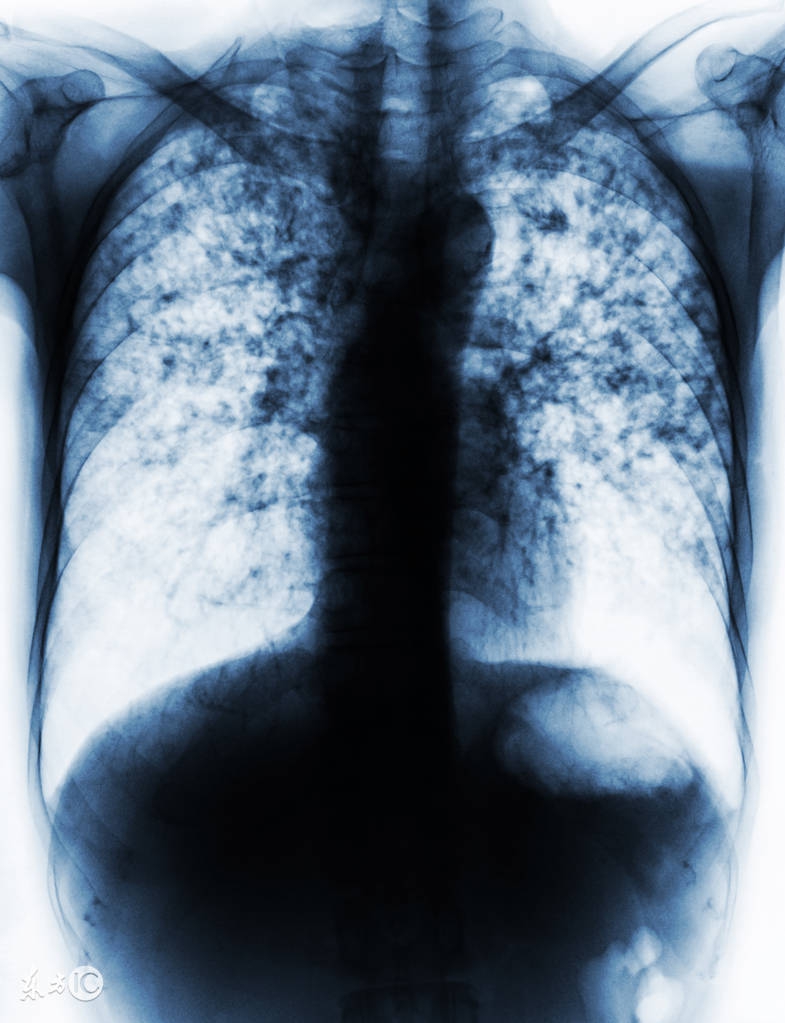

高风险人群:即结核复燃风险至少为正常健康个体6倍者。一般是严重损害免疫功能的病症。比如,HIV感染、淋巴瘤、白血病、化疗、实体器官移植、使用TNF-α*制剂抑**;以及胸片发现纤维结节性改变-----一般认为肺结核已治愈者。